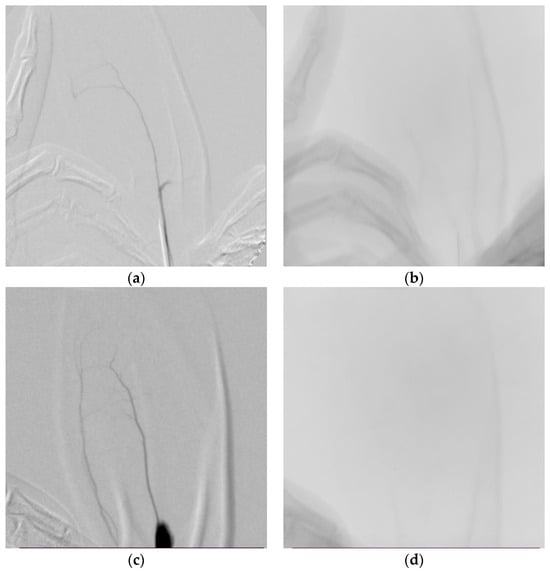

3.3. Angiographic Results